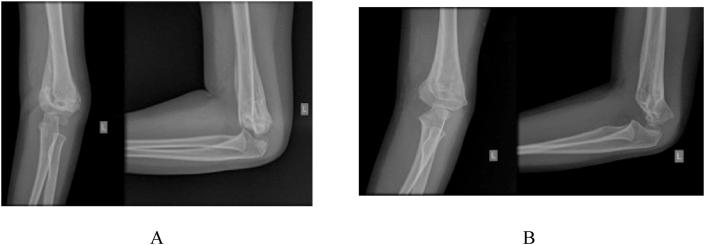

Two cases of malunited supracondylar humerus are described. The first case involves a 3-year-old girl who presented with outstretched and supinated left arm after falling during bike riding 3 weeks earlier. We found no abnormality in radial and median nerve function, but the left arm radiographs showed a callus formation and the early stages of a malunited fracture of the supracondylar humerus. We waited two months for further radiographic evaluation and the radiographs showed the malunited supracondylar humerus with elbow flexion of only 105° and elbow hyperextension of 20°. The cubitus varus was recorded with clinical carrying angle of varus 10°. We used a combination of original French and Dome osteotomy, lateral approach, and our novel fixation technique with excellent results. The second case involved a 8-year-old boy with malunited right elbow and the surgery was done in the same manner, with the result of restoration to normal elbow range of motion. We also assessed the pain score and disabilities of the arm, shoulder and hand (DASH) score and recorded satisfactory results.

描述了两例肱骨髁上骨折畸形愈合的病例。第一例是一名3岁女孩,3周前骑自行车摔倒后出现左上肢伸直旋后位。我们发现桡神经和正中神经功能无异常,但左上肢X线片显示有骨痂形成以及肱骨髁上骨折畸形愈合的早期阶段。我们等待了两个月进行进一步的影像学评估,X线片显示肱骨髁上骨折畸形愈合,肘关节仅能屈曲105°,过伸20°。记录肘内翻时的临床携物角为内翻10°。我们采用了原创的法国截骨术和圆顶截骨术相结合、外侧入路以及我们新颖的固定技术,取得了优异的效果。第二例是一名8岁男孩,右肘畸形愈合,手术方式相同,结果恢复了正常的肘关节活动范围。我们还评估了疼痛评分以及上肢、肩部和手部功能障碍(DASH)评分,结果令人满意。